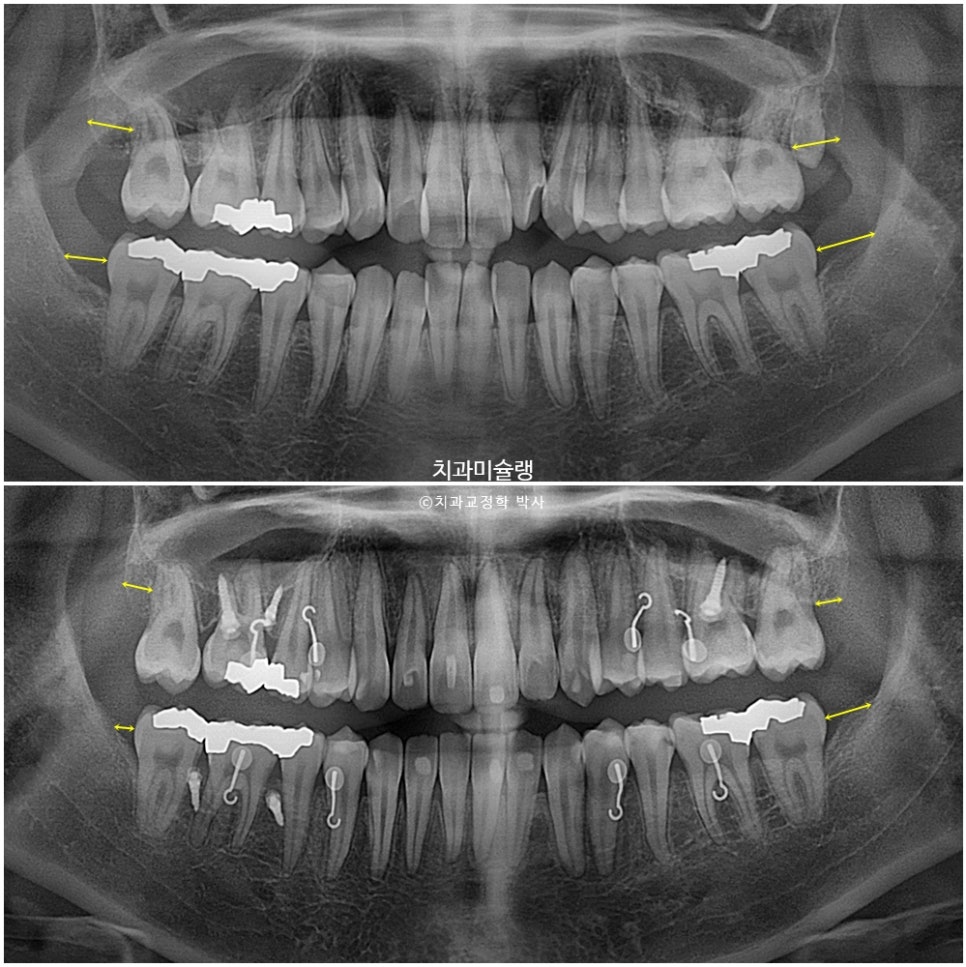

사랑니 공간으로 어금니들이 계획대로 2mm씩 후방이동 한것이 엑스레이로 확인됩니다.

교정치료 기간 동안 치근흡수는 없으며 치근 평행도는 좋습니다.

사랑니 공간으로 어금니들이 잘 이동 된것이 보입니다.